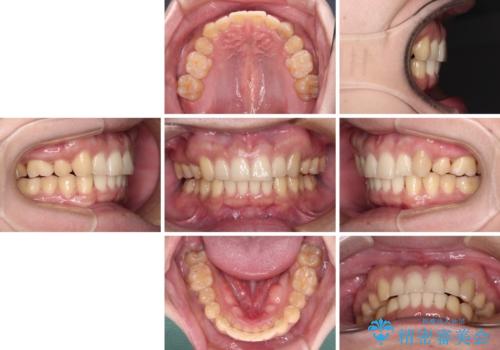

上顎のみの抜歯矯正をインビザラインで行う場合、奥歯の前方移動がインビザラインでは苦手のため、奥歯の咬み合わせが不十分となることがあります。

今回の治療では終了時に奥歯は接触しているものの、接触の程度は物足りないものがある状態でした。今後保定期間に少しずつ奥歯の咬合を改善させていくことになります。